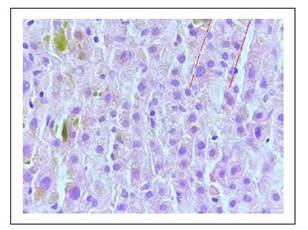

Los hallazgos histológicos en la biopsia hepática se muestran en las Figuras 1 a 6.

Figura 6 Hepatocitos dispuestos en cordones regulares, mostrando regeneración, trabéculas de hasta 3 hileras (líneas rojas).